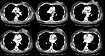

A CT scan of the chest demonstrated the large, cavitary left breast mass, the presence of pathologic adenopathy in the left axilla, and multiple pulmonary metastases.

Soft tissue: